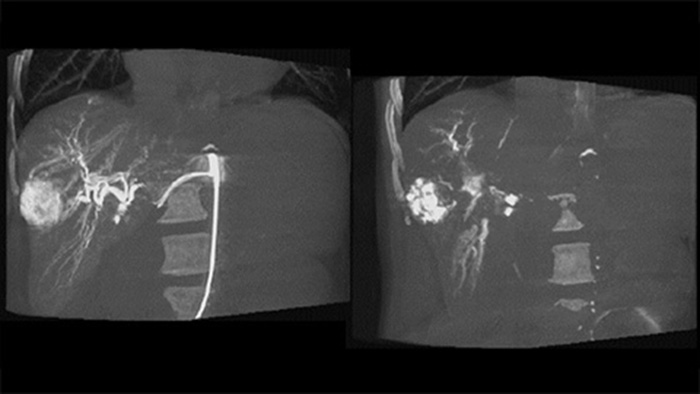

CBCT Dual permite la adquisición 3D de una fase arterial para visualizar estructuras vasculares y una post-arterial (fase retardada) para visualizar la acumulación de medio de contraste, en un solo paso automático5.

Dual View permite la visualización simultánea de dos conjuntos de datos CBCT. Tanto la fase arterial como la retardada pueden mostrarse una al lado de la otra o en una sola vista de superposición fusionada.

Dual View permite la visualización simultánea de la imagen 3D de fase arterial antes de la embolización y la imagen después de la embolización para evaluar el criterio de valoración del tratamiento.